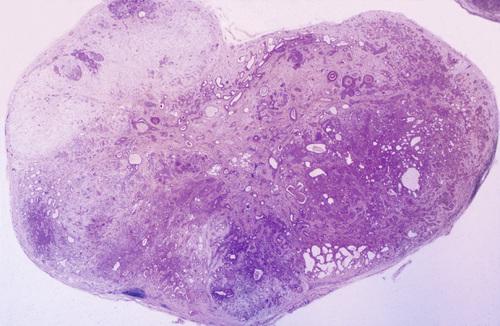

Low-power view showing a well-circumscribed, encapsulated tumor mass. Even at this power, the mixture of glandular epithelium and myoepithelial cells is evident.

pleomorphic adenoma